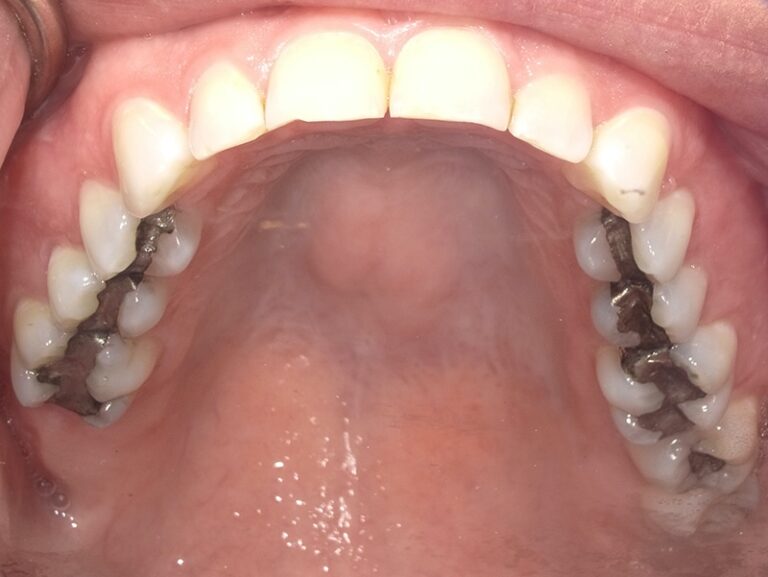

We began this patient's cosmetic journey with SureSmile clear aligners. We were able to accommodate patient's request of a shorter aligner treatment length, and move on to porcelain restorations. We placed 12 upper crowns and 6 lower veneers, thus giving her a beautiful new smile in a shorter timeframe!